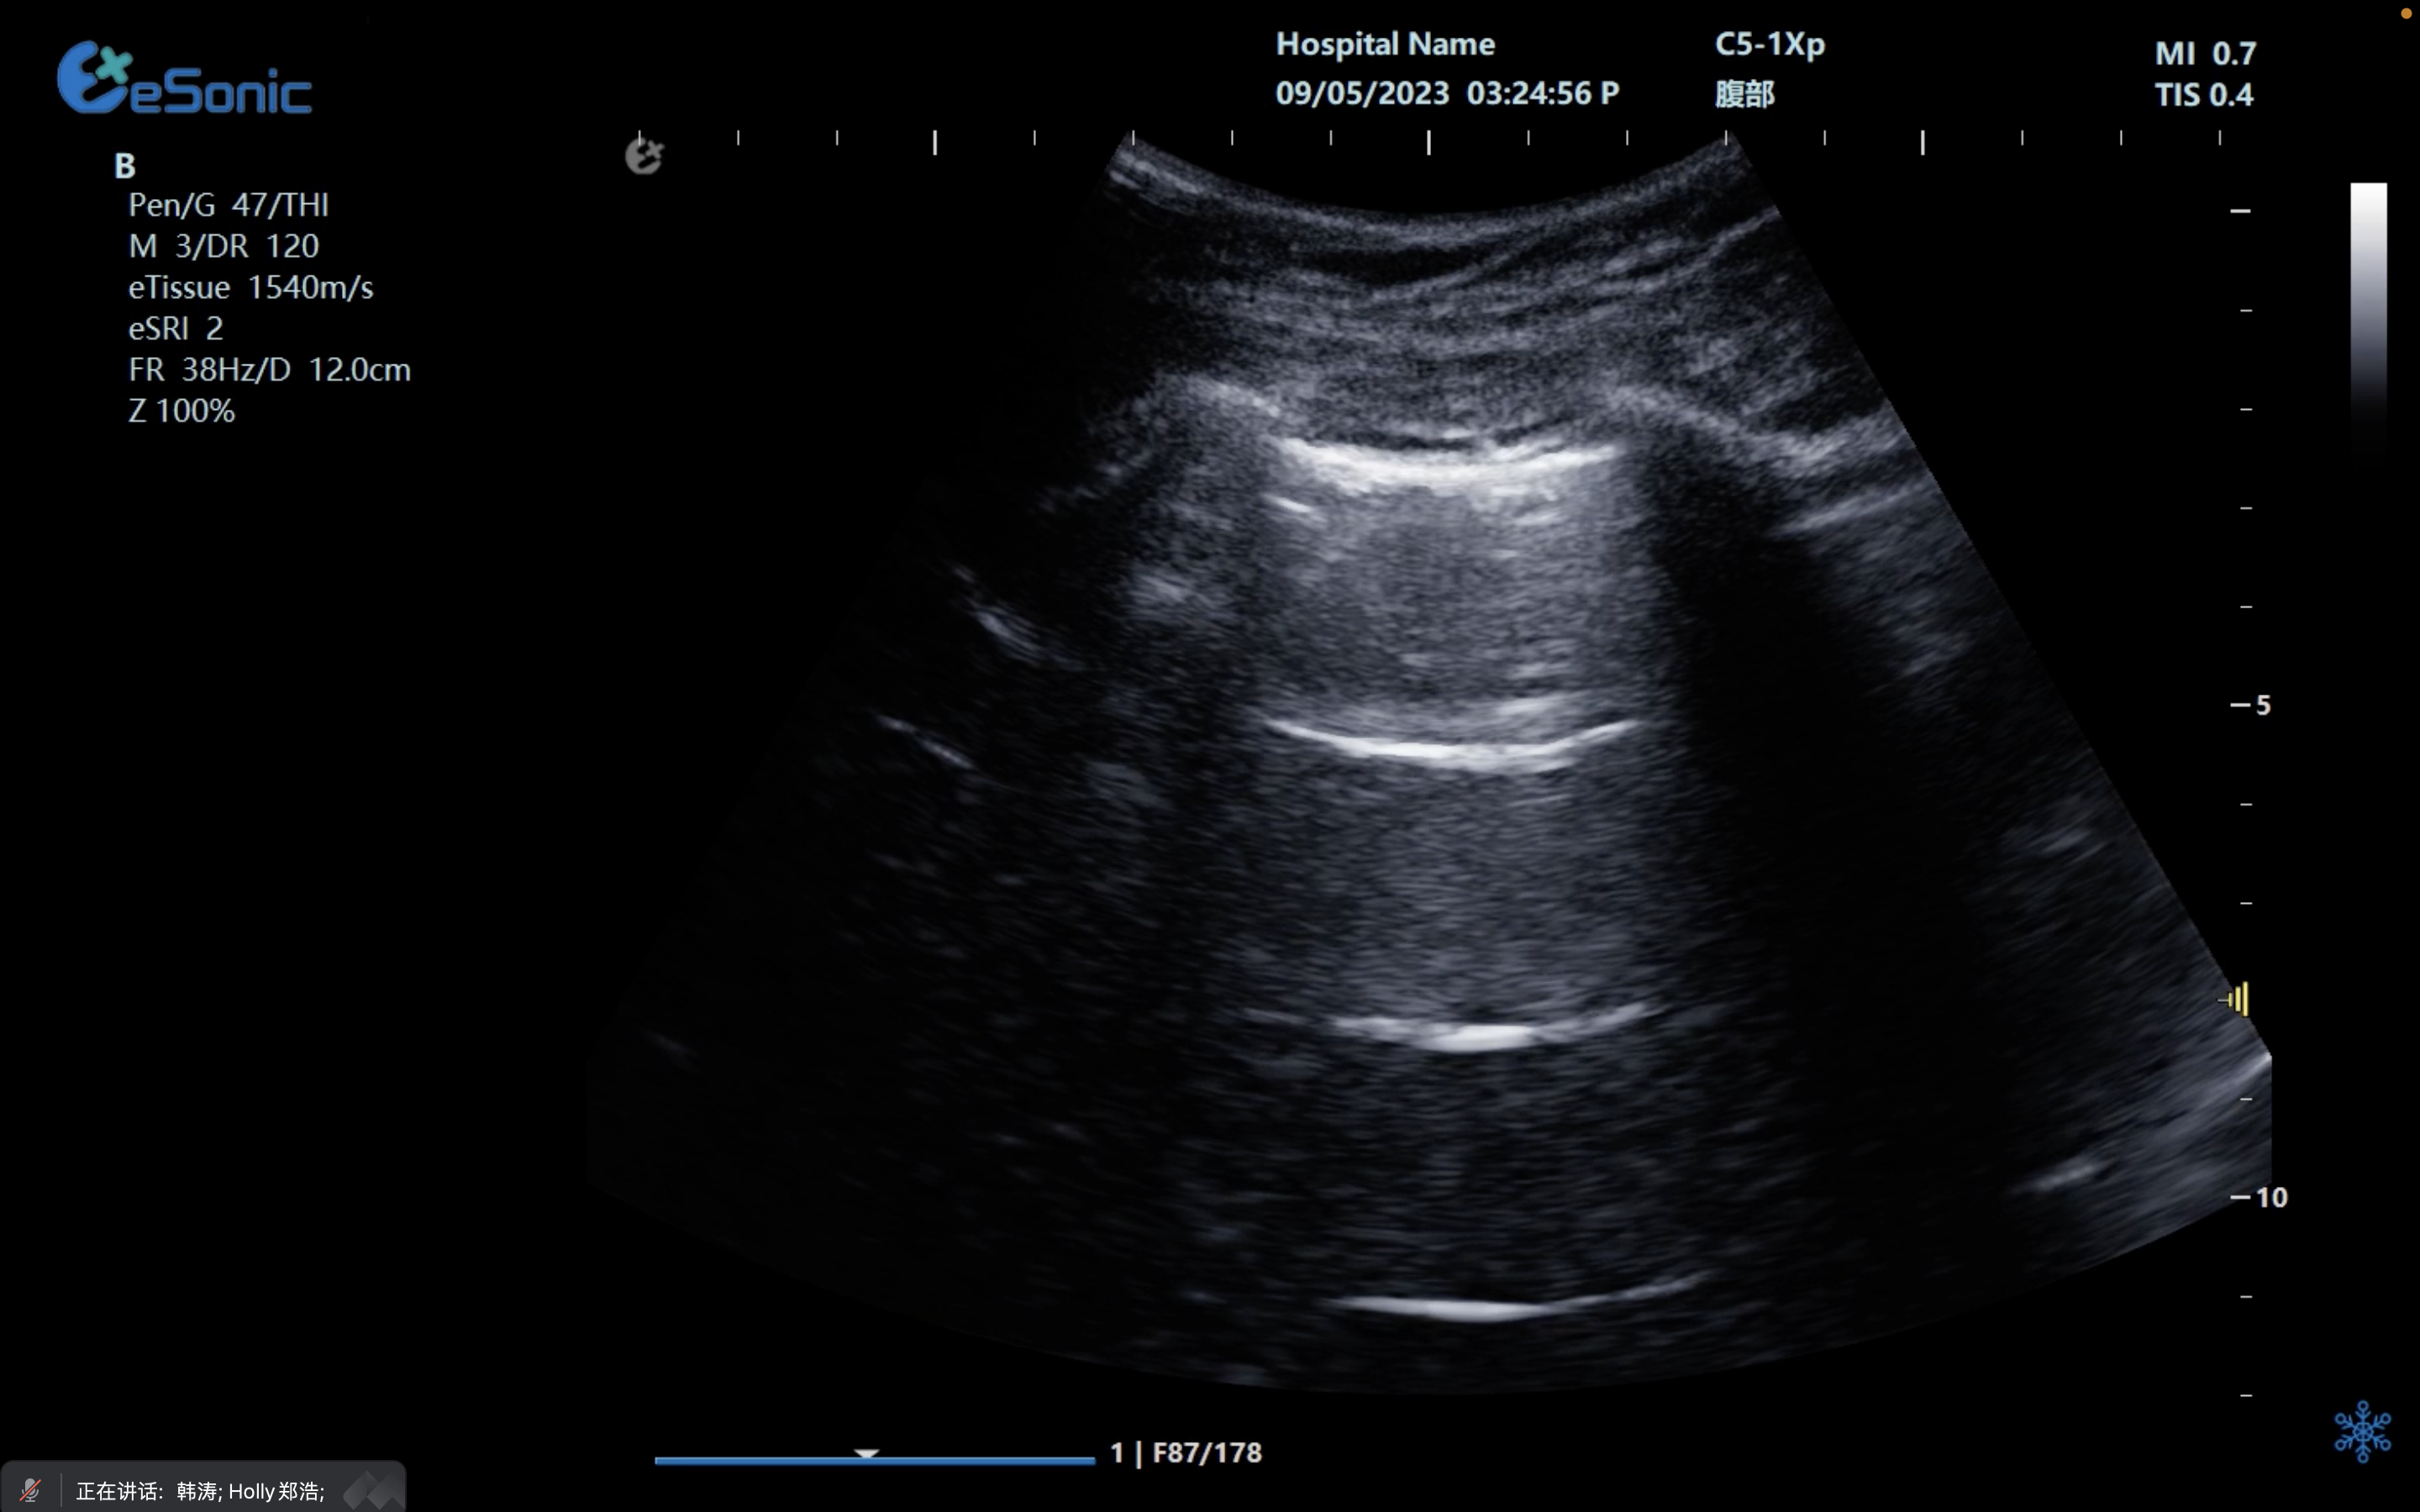

创伤评估FAST

image.png